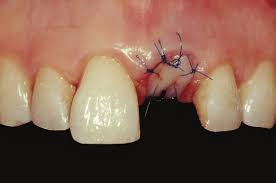

I know the graft will take many months to heal. Losing baby teeth is a rite of passage for children. Correcting bony and tissue defect with synthetic bone graft and soft tissue graft in aesthetic zone. The tooth wasn't stong enogh to pull out in one peice, so she had to lossen the bone around. This means that the site will then be ready to receive a dental implant. How long does it take to recover from a tooth extraction? When i go get a extraction done would i need to get a bone graft done at the same time or can i get it done later? However, because the patient must heal fully from the bone graft before dental implants can be placed, this procedure does extend the treatment timeline. Anyway i'm just wondering how long it takes to be all the way out and if we're in for more pain? It takes about 6 weeks for the jaw bone and gum tissue to repair itself following wisdom teeth extractions. , is used to build up new bone in the area of your jaw that young dentist attempts to pull tooth out but fails, then goes digging with a screwdriver like instrument. Often times a bone graft is placed in the tooth socket to hold the bone open and make it easier to place how does the oral surgeon determine if i am candidate for implants? Bone graft surgery for jaw bone loss socket grafts, ridge splitting, basic augmentation find answers how to fix treat repair replace options.

Dentists will fill the chosen area with this dental bone graft material that will act as a kind of placeholder so that bone healing and remodelling in somes cases, placing an implant at the time of a tooth extraction is possible if the size of the hole is more or less the same as the implant post.